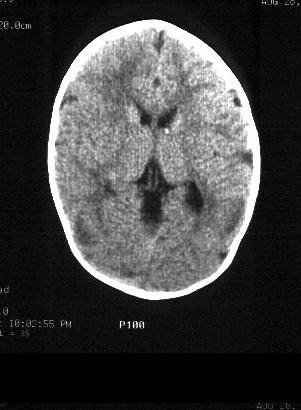

CT of the brain revealed ventriculomegaly and multiple

calcified subependymal nodules in the lateral ventricles. EEG showed a